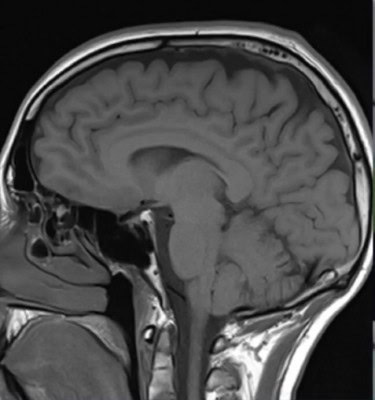

New York, Jan 13 : Researchers have discovered that SARS-CoV-2 can directly infect the central nervous system and have begun to unravel some of the virus’s effects on brain cells.

The study, that used both mouse and human brain tissue, indicates that SARS-CoV-2 can affect many other organs in the body, including, in some patients, the central nervous system, where infection is associated with a variety of symptoms ranging from headaches and loss of taste and smell to impaired consciousness, delirium, strokes and cerebral haemorrhage.

“Understanding the full extent of viral invasion is crucial to treating patients, as we begin to try to figure out the long-term consequences of Covid-19, many of which are predicted to involve the central nervous system,” said researcher Akiko Iwasaki, a professor at Yale University.

The researchers found that the virus was able to infect neurons in these organoids and use the neuronal cell machinery to replicate. The virus appears to facilitate its replication by boosting the metabolism of infected cells, while neighbouring, uninfected neurons die as their oxygen supply is reduced.

SARS-CoV-2 was also able to infect the brains of mice genetically engineered to produce human ACE2, causing dramatic alterations in the brain’s blood vessels that could potentially disrupt the organ’s oxygen supply, the team said.

SARS-CoV-2 was detected in the cortical neurons of one of these patients, and the infected brain regions were associated with ischemic infarcts in which decreased blood supply causes localized tissue damage and cell death. Microinfarcts were detected in the brain autopsy of all three patients.